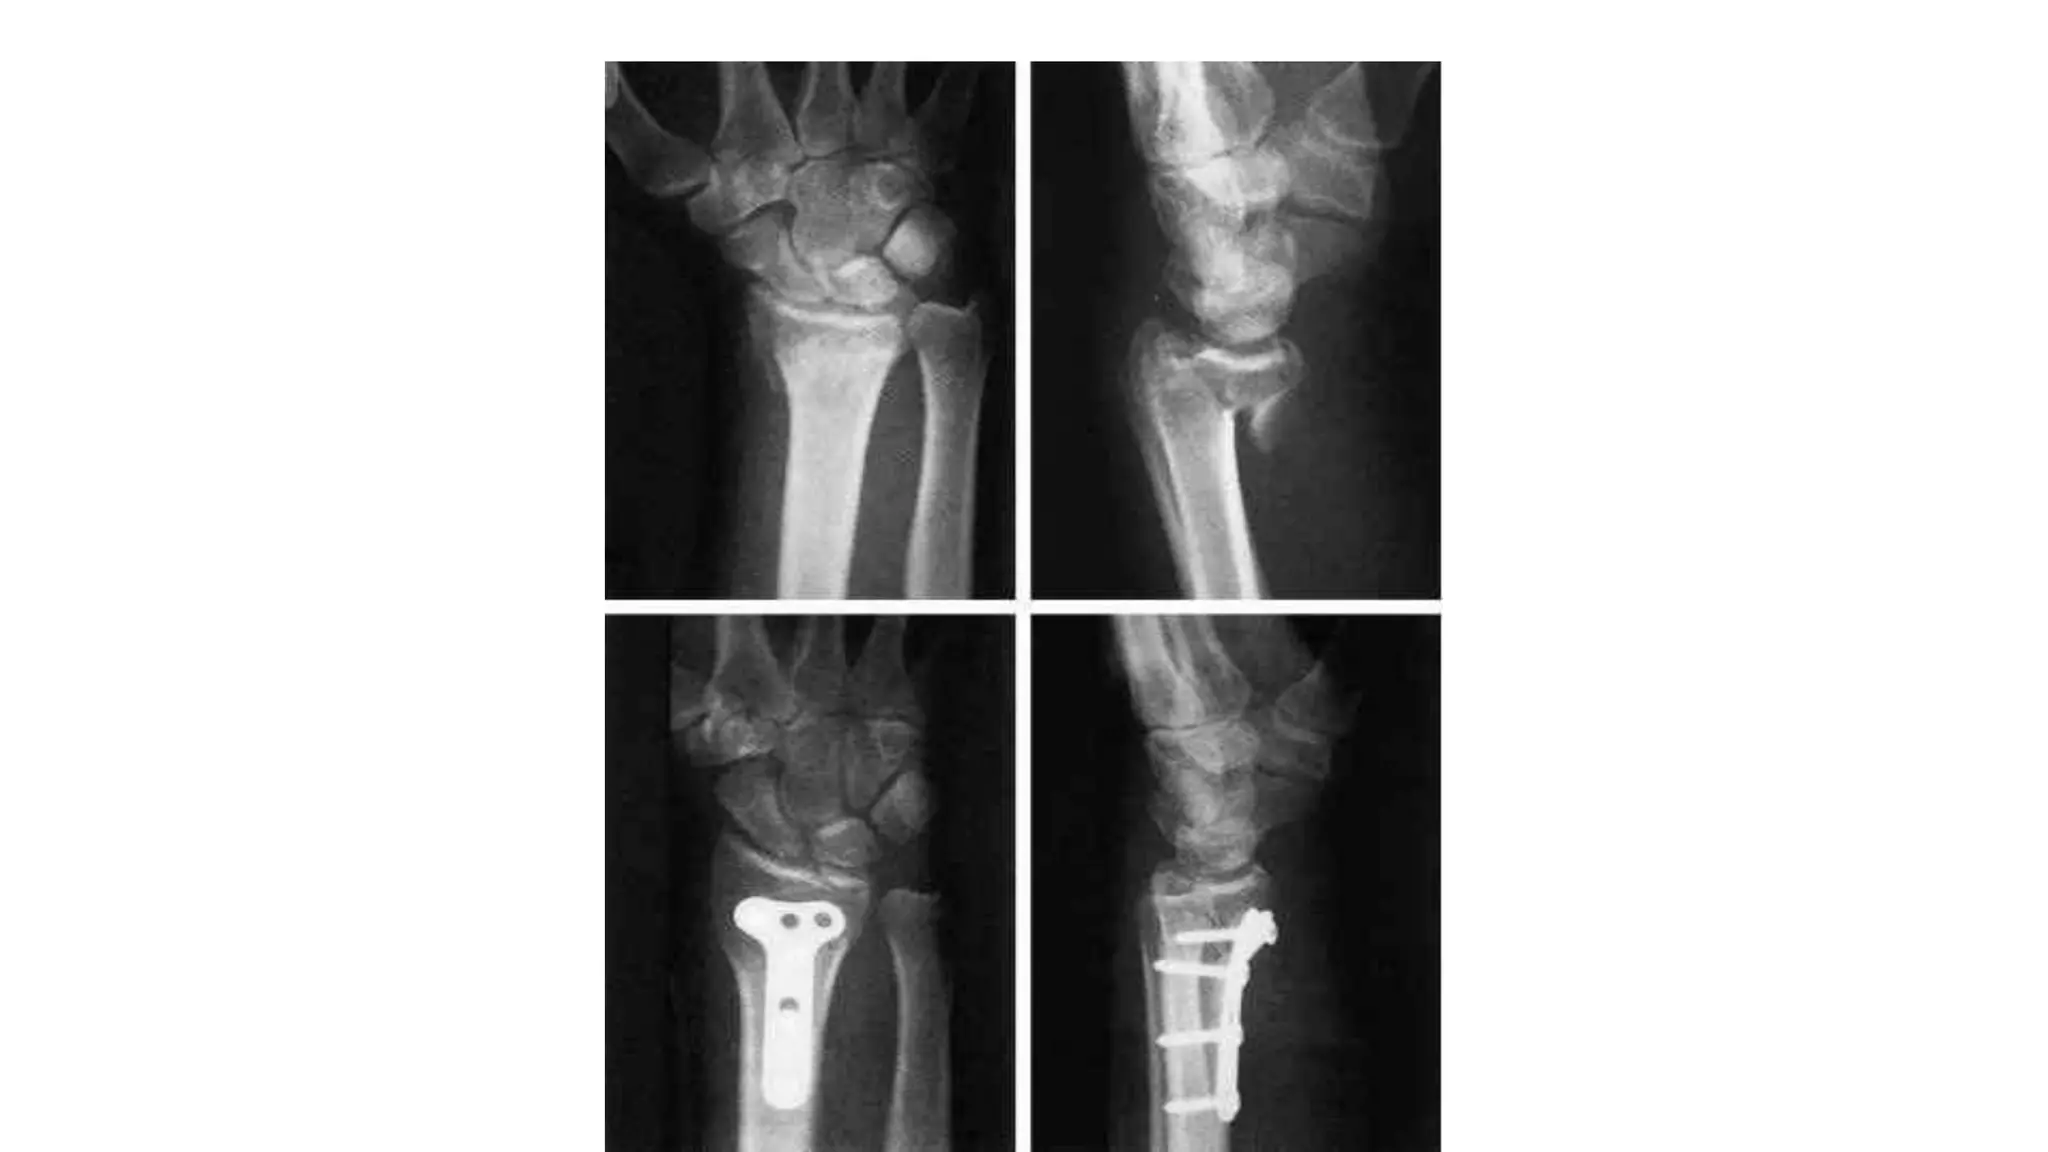

Fragmented intra-articular fractures

 In the young adult, a fragmented intra-articular fracture is a high-

energy injury.

 A poor outcome will probably result unless intra-articular congruity,

fracture alignment & length are restored & movements started as

soon as possible.

2. Surgery :

- All fragments must be

reduced into a good

position & held in a stable

manner.

- Volar locking plate are

particularly useful.

Fragmented intra-articular fractures In the young adult, a fragmented intra-articular fracture is a high- energy injury.  A poor outcome will probably result unless intra-articular congruity, fracture alignment & length are restored & movements started as soon as possible.

Treatment 1. Conservative : -Simple manipulation under anesthesia & cast may be helpful. - X-rays are needed at about 07 days. - If the anatomy is not restored, then either closed reduction with percutaneous wires & an open reduction may well be necessary.

• 49.

2. Surgery : -All fragments must be reduced into a good position & held in a stable manner. - Volar locking plate are particularly useful.